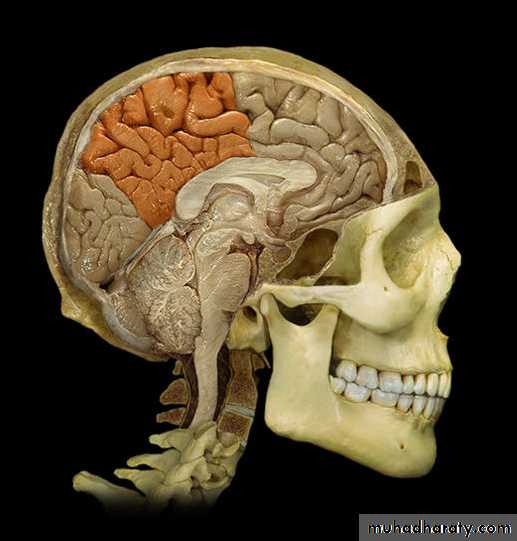

Lobes of Cerebral Hemisphere

Five lobes

Frontal lobe

Parietal lobe

Temporal lobe

Occipital lobe

Insular lobe

Parietal lobeOccipital lobe

• 2. Medial surface:

• Paracentral

• lobule

• Precuneus

• Cuneus